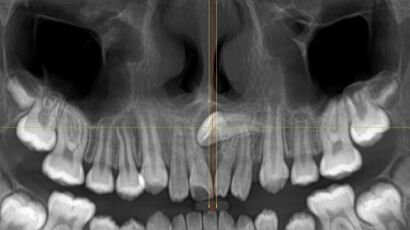

La tomografía computarizada dental maxilar es una técnica de imagen avanzada que permite obtener…

La tomografía axial computarizada (TAC) es una técnica de imagen médica que utiliza rayos…